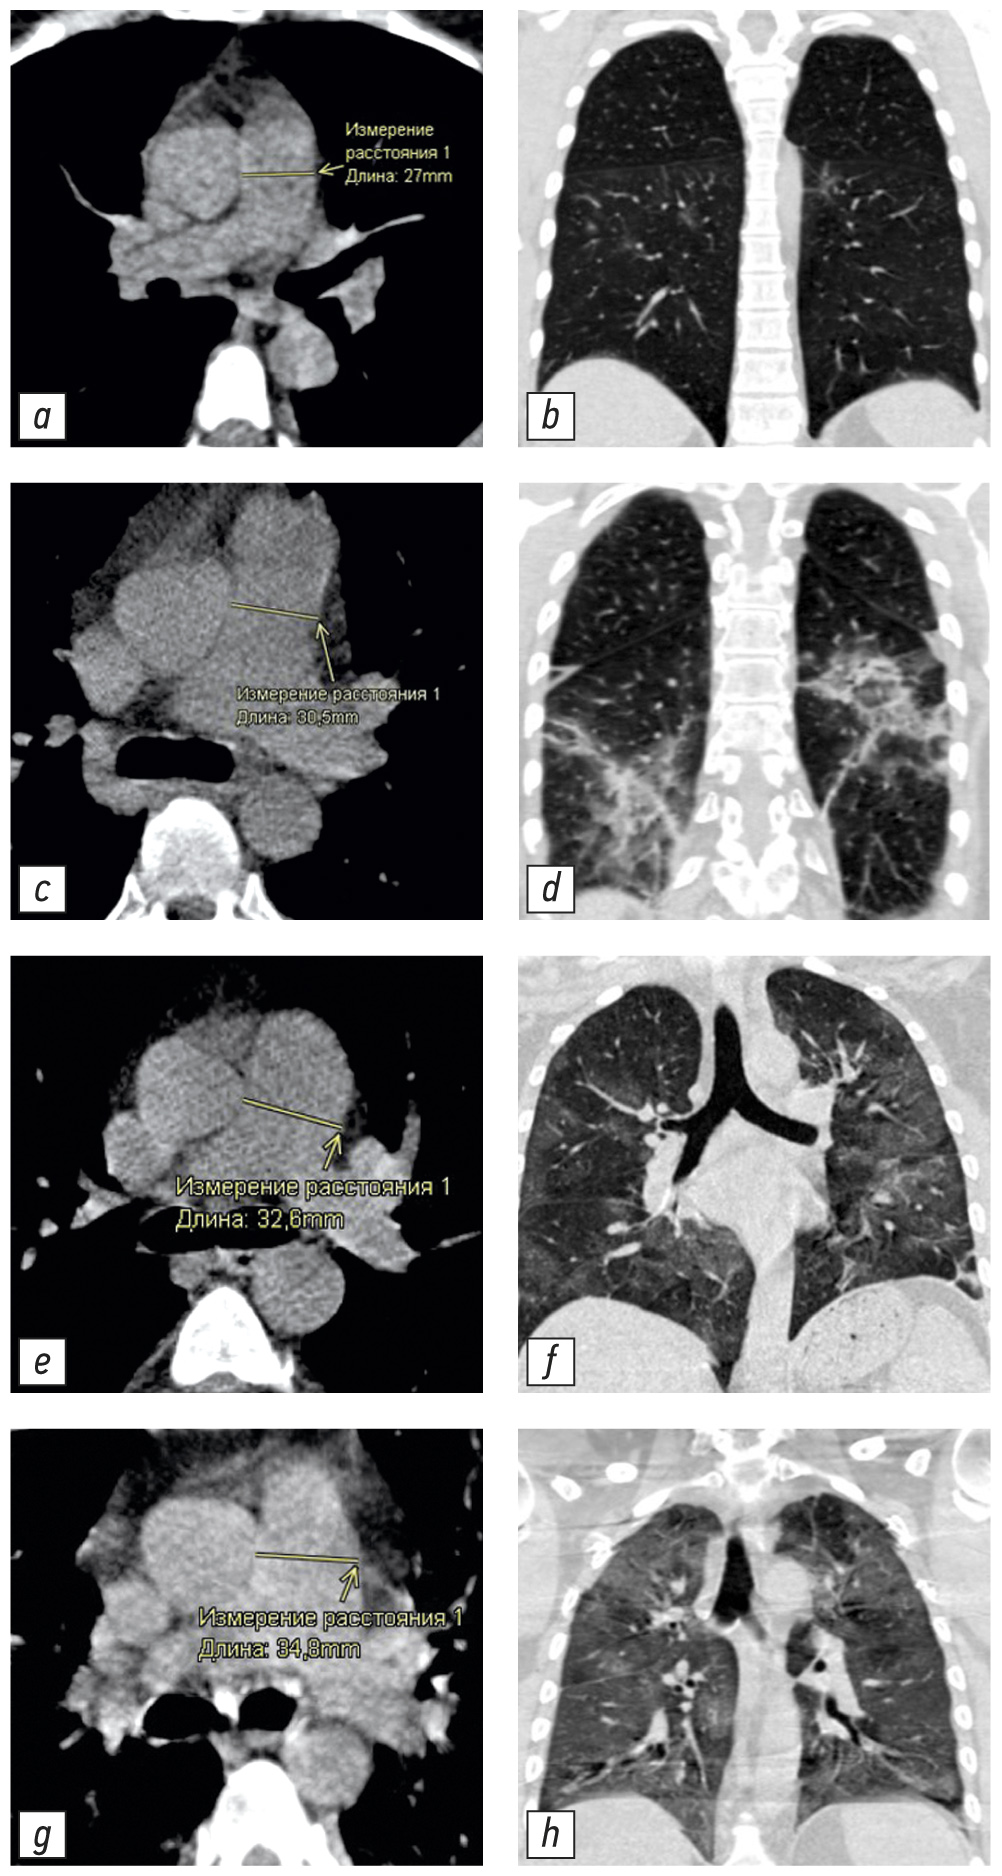

不同体积肺实质病变患者的CT图像及相应的肺动脉测量值在图3提出。

图 3 具有不同 PA 直径和肺部受累程度的 CT 图像示例:a、b - 未扩张的 PA(27.0 毫米),CT-1 肺部受累程度(小于 25%); c, d - 肺损伤程度 CT-2 (25-50%) 增大的 PA (30.5 毫米); e, f - 扩张的 PA (32.6毫米),肺损伤程度为 KT-3 (50–75%); g, h - 肺损伤程度 CT-4(大于 75%)的扩张 PA(34.8毫米)。 CT - 计算机断层扫描; CT 1-4 - 用于视觉评估患者全身状况严重程度对 COVID-19 肺部变化的放射学迹象的性质和严重程度的依赖性的改编量表; PA-肺动脉。